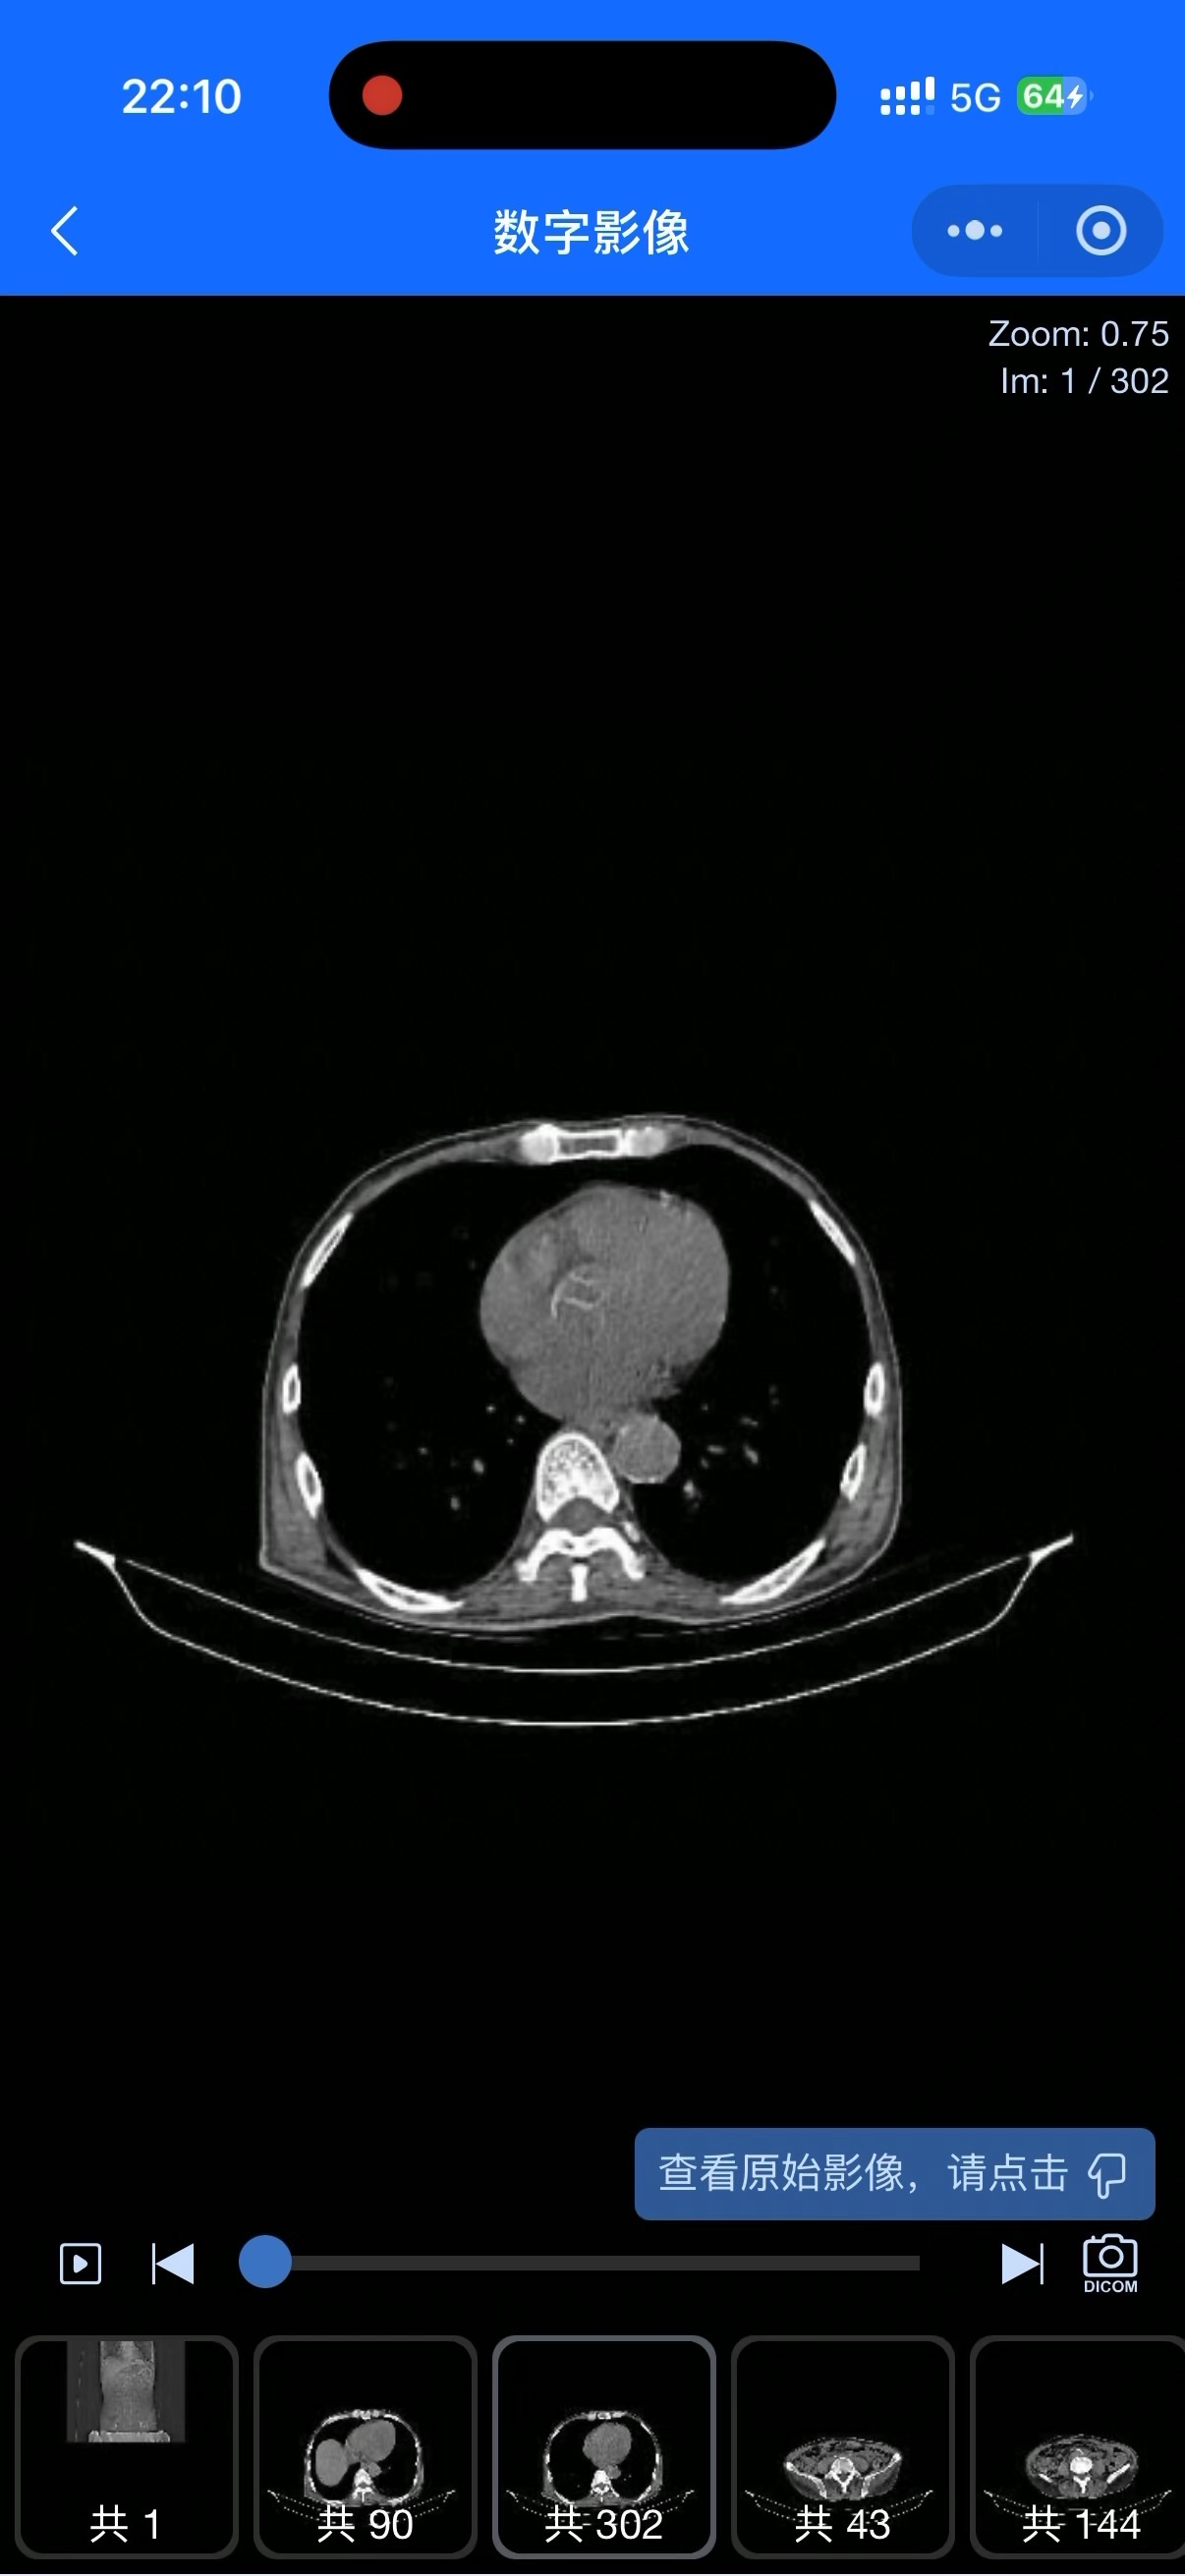

患者54岁,吉兰巴雷综合征病史。既往未行肠镜检查。7月份突然大量便血,CT提示结肠穿孔,行手术治疗及乙状结肠双腔造瘘,发现结肠组织较硬,但未行病理检查。术后持续粘液便,近一周出现肛门排出黏液脓血便;造瘘处便黄,潜血-。CT提示盆腔积气,消化道穿孔待除外、腹腔感染?但无腹痛及腹膜刺激征。住院期间持续发热,提问最高39摄氏度,有抑郁倾向,问话懒答。